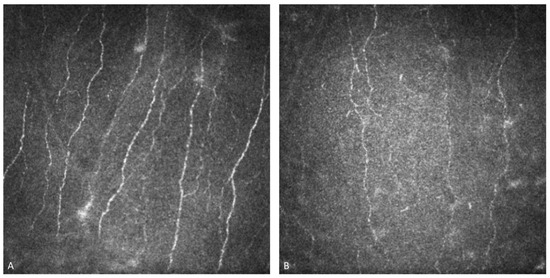

Figure 4. In vivo confocal microscopy examination of the sub-basal nervous plexus of a healthy cornea (A) compared with a Fabry disease patient’s cornea (B), characterized by a significant reduction in the length, number, and density of the nerve fibers, and by an increased tortuosity.

IVCM examination of the corneal nerve plexus of FD patients shows a significant reduction in the length, number, and density of the nerve fibers, along with increased tortuosity, even in the absence of corneal deposits. Hyperreflective dots and alteration in the corneal nerve plexus may be detected on IVCM, even if no other signs and symptoms are evident. Therefore, it is important to consider this real-time and noninvasive tool for early diagnosis in patients at risk [39].

Corneal nerve fiber density in female and male patients who are treated with ERT is reduced compared with control subjects. Corneal nerve branch density is reduced in females not on ERT and in female or male patients on ERT compared to control subjects. Furthermore, corneal nerve length does not differ in FD females according to ERT status, but is significantly reduced in males on ERT compared with controls. These findings underscore the importance of using IVCM not only for early diagnosis but also for ongoing monitoring of corneal nerve health in FD patients, regardless of their treatment status [49] (Figure 4).